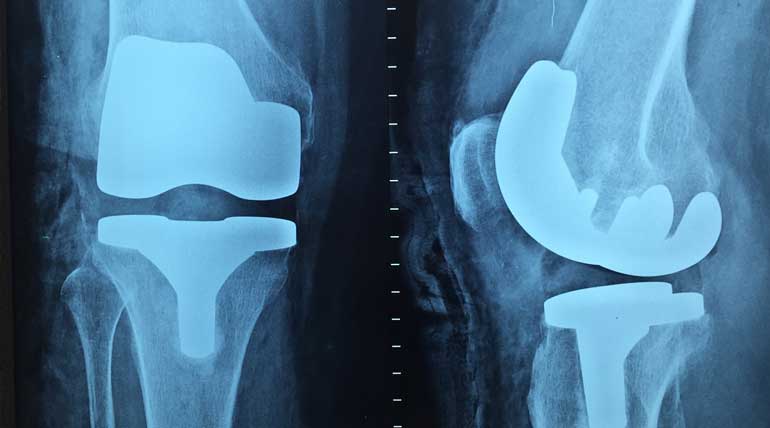

• Artificial knees fixed by early operations wear out within the next 20 years

Knee surgery details that help to have a happy life: Many people do their knee surgery either too late or too early, confirms a new study. 90 % of people wait too long, and 25 % do premature knee surgery in the US is the finding of the study.

More than 630 million people or 15 % of the population are affected by osteoarthritis. Hence this study published on January 13 in Bone and Joint Surgery journal gains importance.